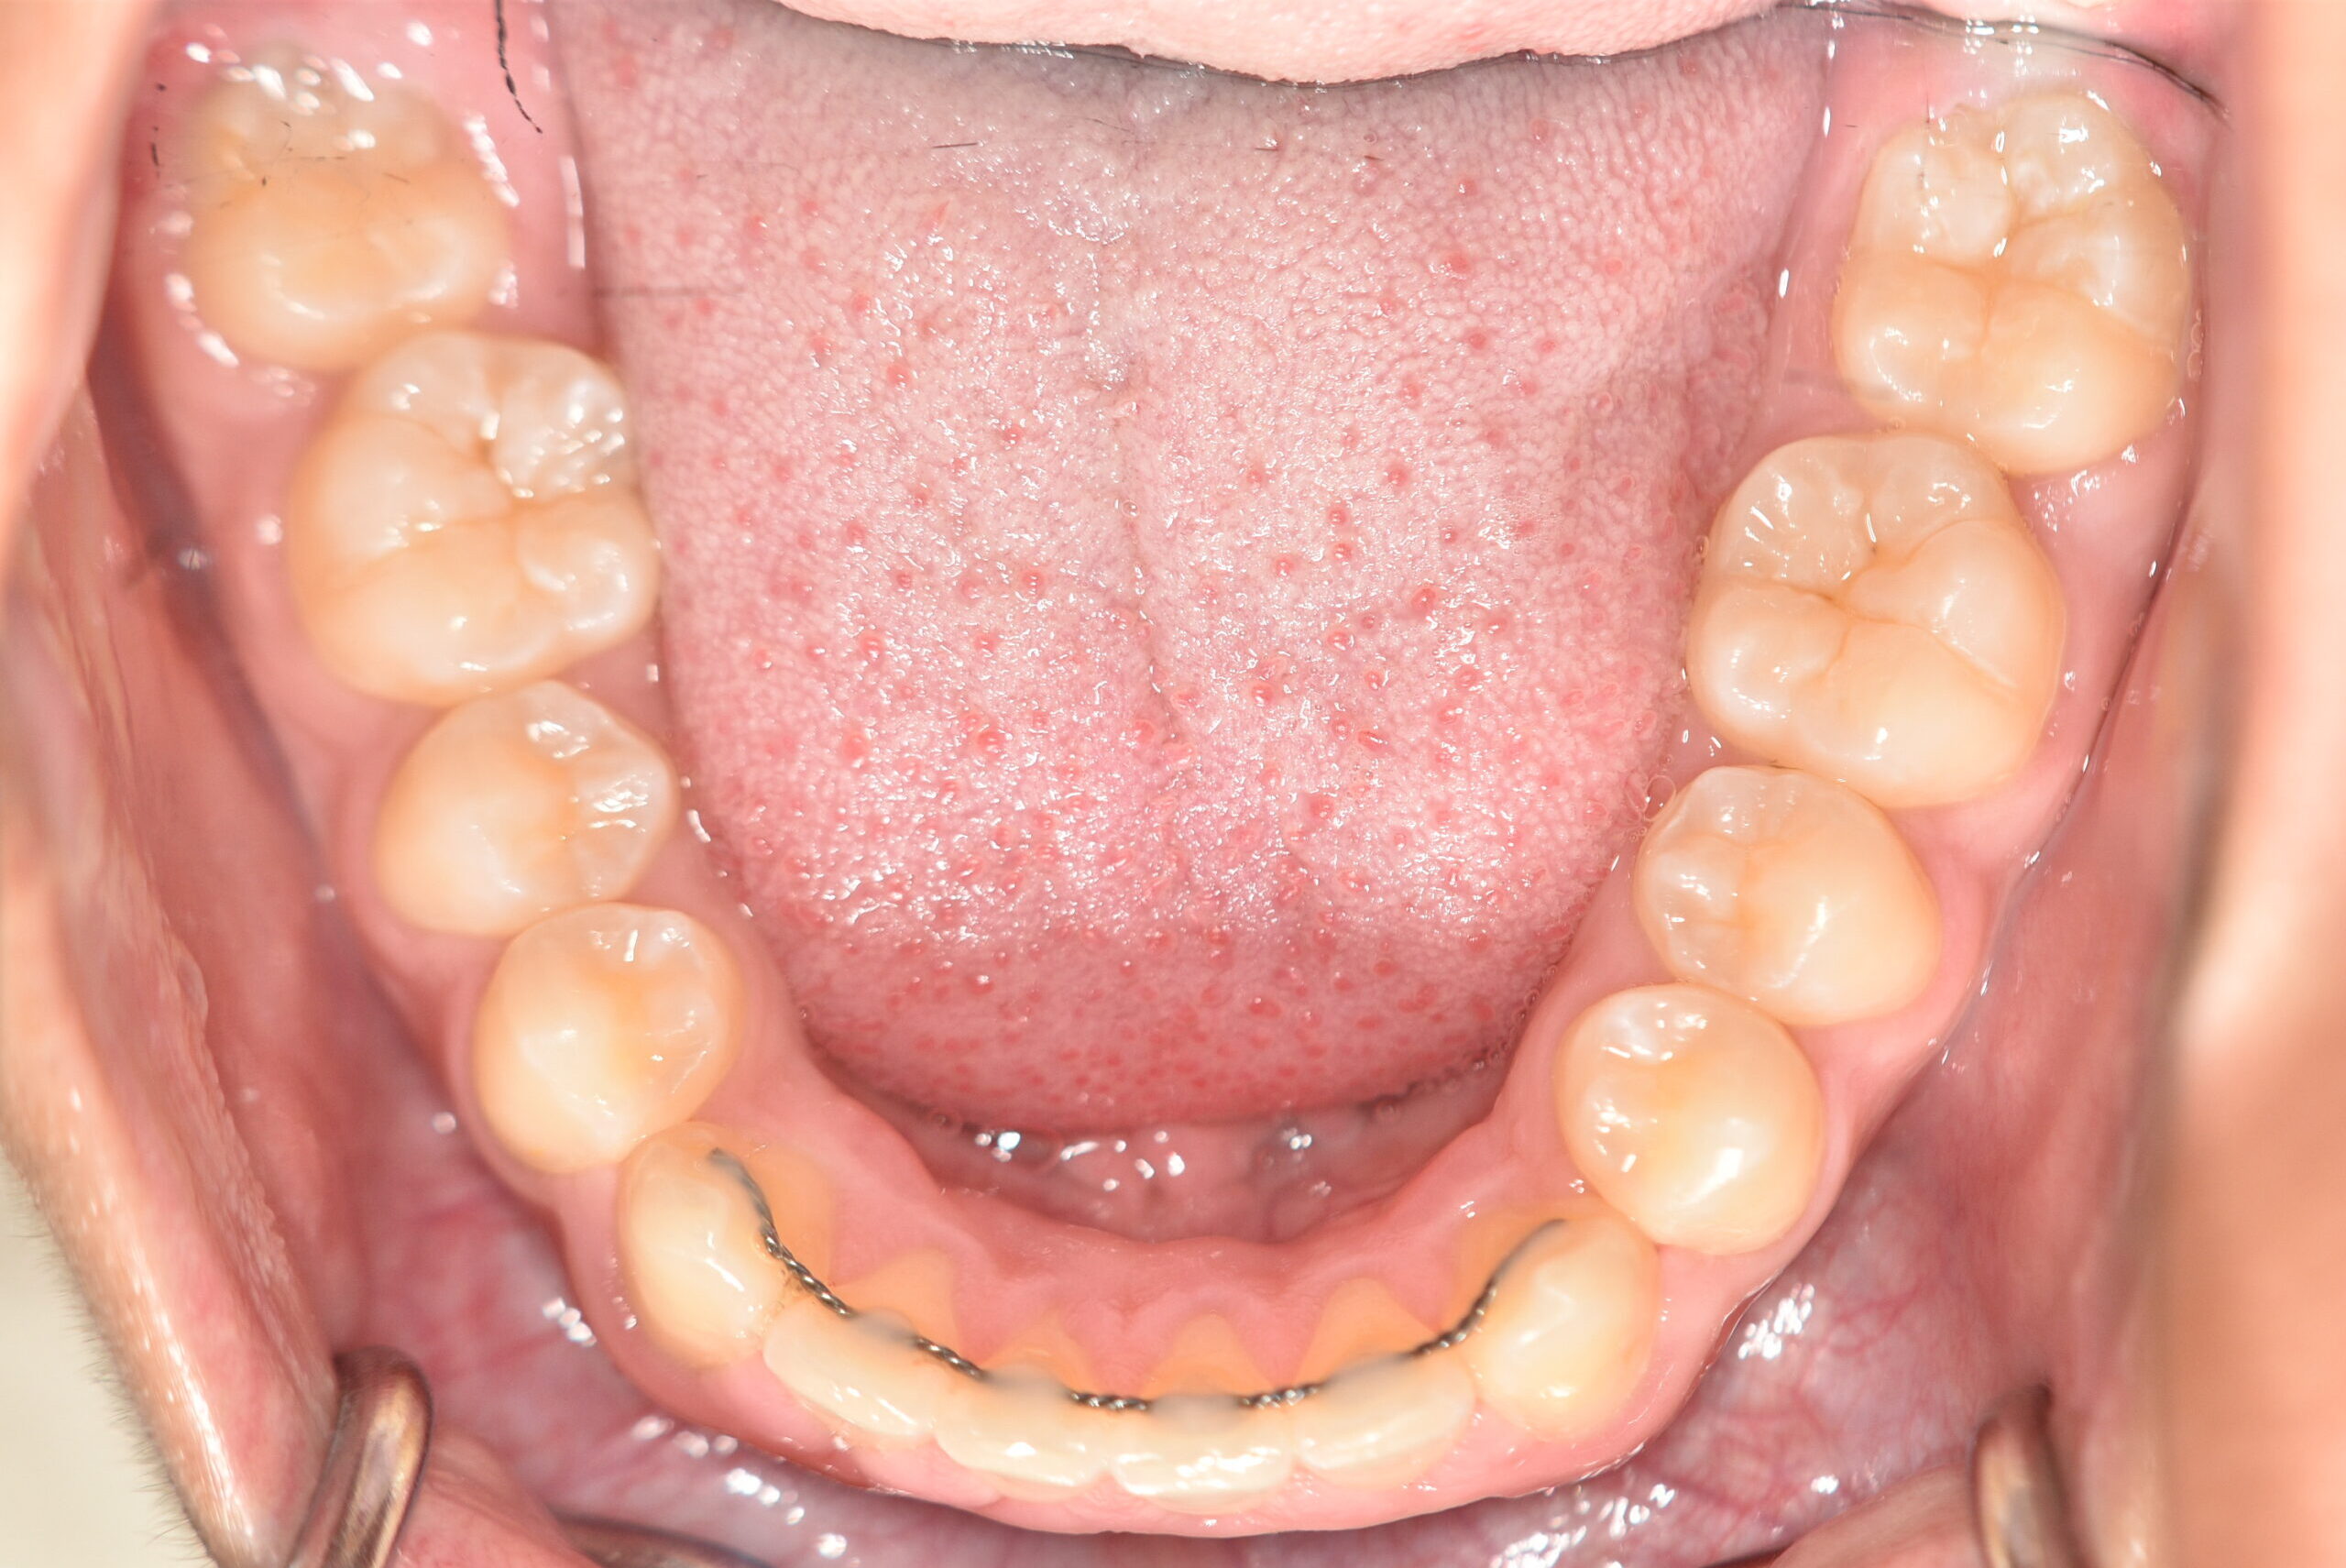

動的治療終了時

症例 症例 症例 症例